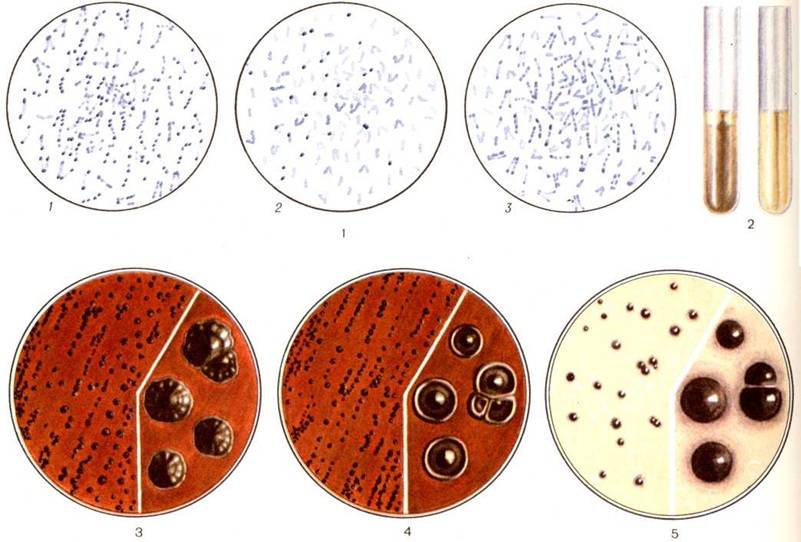

ДифтерияДифтерия (греческий diphthera кожа, плёнка) — острая инфекционная болезнь с воздушно-капельным путём передачи возбудителя, характеризующаяся воспалительным процессом в зеве, гортани, трахее, реже в других органах с образованием фибринозных налётов и явлениями интоксикации. Чаще поражает детей. Оглавление Патогенез и патологическая анатомия ИсторияКлассическое описание и объединение различных форм болезни сделал Бретонно (P. F. Bretonneau) в 1826 год; он дал ей название дифтерит. А. Труссо предложил ныне общепринятое название дифтерия. В 1883—1884 годы Клебс (T. A. E. Klebs) и Ф. Леффлер открыли и выделили в чистом виде возбудителя болезни. В 1892—1894 годы Э. Беринг и одновременно Э. Ру и Я. Ю. Бардах получили противодифтерийную сыворотку. Введение в практику серотерапии явилось важнейшей вехой в истории Дифтерия. В 1902 год С. К. Дзержговский доказал возможность активной иммунизации человека против Дифтерия В 1913 год Э. Беринг разработал метод активной иммунизации смесью токсина и антитоксина. Г. Рамон в 1923 год предложил иммунизацию дифтерийным анатоксином. В разработку и усовершенствование противодифтерийных прививок большой вклад внёс П. Ф. Здродовский. ЭтиологияВозбудитель Дифтерия — Corynebacterium diphtheriae — относится к роду Corynebacterium (Lehmann, Neumann, 1896), группе коринеформных бактерий (Bergey’s Manual of Determinative Bacteriology, 1974); морфологически представляет собой полиморфные тонкие, слегка изогнутые палочки 0,5 × × 1,0—3,0—5,0 микрометров (встречаются ветвящиеся, сегментированные и кокковидные формы — цветной рисунок 1). При электронно-микроскопическом изучении (рисунок 1) видна трёхслойная клеточная стенка, у многих штаммов есть микрокапсула (Е. И. Нехотенова с соавторами, 1963; И. С. Барбан, 1964). В цитоплазме имеются нуклеоид, внутрицитоплазматические мембраны — мезосомы, вакуоли, а также как необязательный компонент — скопления полифосфата, так называемый зерна волютина или Бабеша—Эрнста. При окраске фиксированных бактерий Дифтерия анилиновыми красителями зерна окрашиваются метахроматически по отношению к цитоплазме; скопления нуклеиновых кислот в клетках придают им полосатость. Бактерии Дифтерия грамположительны. Благодаря делению клеток в виде излома и расщепления они нередко располагаются под углом друг к другу. Жгутиков не имеют, спор^ не образуют. Морфологически Cor. diphtheriae бывает неотличима от многих штаммов других коринебактерий, встречающихся на коже и слизистых оболочках человека (так называемый дифтероидов), и для определения видов внутри рода требуется изучение комплекса культуральных и биохимический признаков. По устойчивости к воздействию факторов окружающей среды бактерии Дифтерия не отличаются от неспорообразующих патогенных бактерий. Возбудитель Дифтерия весьма чувствителен к действию многих антибиотиков — пенициллина, тетрациклина, эритромицина. Однако в носоглотке больных и носителей, несмотря на лечение этими препаратами, бактерии Дифтерия могут находиться длительное время. |

Возбудитель Дифтерия — гетеротроф (смотри полный свод знаний Гетеротрофные организмы). При его культивировании в искусственных условиях питательные среды должны содержать в качестве источников углерода и азота аминокислоты — β-аланин, цистин, метионин, валин и некоторые другие [Мюллер (J. Mueller), 1938]. Оптимальное значение pH 7,6; оптимальная температура культивирования 36—38°. Микроб является факультативным анаэробом (смотри полный свод знаний Анаэробы).

Для роста Cor. diphtheriae применяют питательные среды, приготовленные на основе обычных бульонов — мясопептонного (смотри полный свод знаний Бульон мясопептонный), Мартена (смотри полный свод знаний Мартена бульон, пептон), Хоттингера, с добавлением 5—15% сыворотки или гемолизированной крови. В конце 19 век Э. Ру предложил использовать свернувшуюся лошадиную сыворотку; Ф. Леффлер перед свёртыванием добавлял к ней 25% бульона, содержащего 1% глюкозы. На поверхности плотных кровяных или сывороточных сред дифтерийные культуры развиваются макроскопически через 18—24 часа. Колонии круглые, 0,5—1,0 миллиметров в диаметре, суховатые, кремовато-жёлтого цвета, не сливающиеся даже при сплошном посеве, иногда крошатся при прикосновении петлёй. Cor. diphtheriae расщепляет без газа с образованием кислот глюкозу и мальтозу, изредка сахарозу, а некоторые разновидности — крахмал, гликоген и декстрин. Наиболее постоянным признаком для всех штаммов Cor. diphtheriae является расщепление цистина с образованием H2S, а также отсутствие ферментов уреазы и фосфатазы. Способность коринебактерий Дифтерия и некоторых других восстанавливать металлический теллур из его солей также используется в целях дифференциальной диагностики. Важно, что теллуриты К и Na являются не только субстратом восстановления, но и ингибиторами микрофлоры, встречающейся в зеве.

Вид Cor. diphtheriae неоднороден. Он подразделяется на токсигенные и нетоксигенные разновидности, а также на различные культурально-биохимический, серологические и фаготипы. Выделяют два основных культурально-биохимический типа: гравис и митис, а также ряд промежуточных форм — тип интермедиус [Андерсон (J. S., Anderson) с соавторами, 1931, 1933] и тип минимус (Фробишер, 1946). Наиболее чётко типы дифференцируются по форме колоний на среде Мак-Лауда — варианте кровяного теллуритового агара. Колонии типа гравис (цветной рисунок 3) через 48—72 часа роста имеют диаметром 1,0—2,0 миллиметров, волнистые края, отличаются радиальной исчерченностью и уплощённым центром, напоминают цветок маргаритки. Цвет их благодаря восстановлению теллура и соединению его с одновременно образующимся сероводородом (H2S) серо-чёрный, поверхность колоний матовая. На бульоне представители типа гравис растут в виде крошащейся плёнки. Ок. 90% штаммов расщепляет крахмал, декстрин и гликоген с образованием кислот. Второй биотип — митис — на поверхности кровяного теллуритового агара формирует круглые, слегка выпуклые, черные, матовые колонии, нередко окружённые валиком с ровными краями, диаметром 1,0—2,0 миллиметров (цветной рисунок 4); на бульоне растёт обычно в виде равномерной мути. Большинство штаммов не ферментирует крахмал, декстрин и гликоген. Колонии типа интермедиус круглые и выпуклые, мельче, чем у типа митис, не имеют валика, черные, с блестящей поверхностью; отношение к крахмалу и другим полисахаридам непостоянное. Все биотипы продуцируют идентичный токсин, хотя токсигенность присуща типу гравис. Обозначения типов были введены англ. авторами (Андерсон с соавторами, 1931), полагавшими, что гравис ассоциируется с более тяжёлыми, а митис — с более лёгкими формами болезни. Последующие наблюдения не смогли подтвердить чёткой связи между биотипами и формами заболевания Дифтерия, а также степенью их эпидемиологической опасности.

На поверхности сред в чашках через 24—48 часов появляются хорошо развитые колонии бактерий Дифтерия (цветной рисунок 5), которые используют для выделения чистых культур с целью последующей идентификации (смотри полный свод знаний Идентификация микробов). Установление принадлежности культуры к роду коринебактерий проводится на основании морфологически и культуральных особенностей; идентификация вида Cor. diphtheriae — на основании комплекса биохимический свойств (способности продуцировать H2S на средах с цистином и неспособности расщеплять мочевину). Биотипы гравис и митис различаются по ферментации крахмала с учётом морфологии колоний. Токсигенность определяется in vitro методом преципитации в агаре по Оухтерлоню. Количественное определение степени токсигенности возможно на живых моделях — морских свинках или 9-дневных куриных эмбрионах. Учитывая многообразие тестов и необходимость получения ответа в кратчайшие сроки, наиболее рациональным является следующий порядок действий: выросшая на поверхности элективной среды в чашке хорошо развитая подозрительная колония отсеивается одновременно на среду Леффлера или Ру в пробирку (для получения чистой культуры), на поверхность среды для определения токсигенности (в виде «бляшки») и в столбик среды с цистином. По возможности делают отсевы двух или более колоний. Через 24 часа культуру изучают в микроскопе. При подозрении на принадлежность к роду коринебактерий учитывается результат на среде с цистином (проба Пизу; цветной рисунок 2) и ставится проба на уреазу. На этом этапе (то есть через 48 часов от начала исследования, если не применялся метод обогащения) возможна выдача окончательного ответа. К этому же сроку могут появиться линии преципитации на среде для определения токсигенности; в случае их отсутствия результаты определяются ещё через одни сутки (то есть через 72 часа от начала исследования). Выросшая культура бактерий Дифтерия используется для определения биотипа, серотипа и фаготипа.